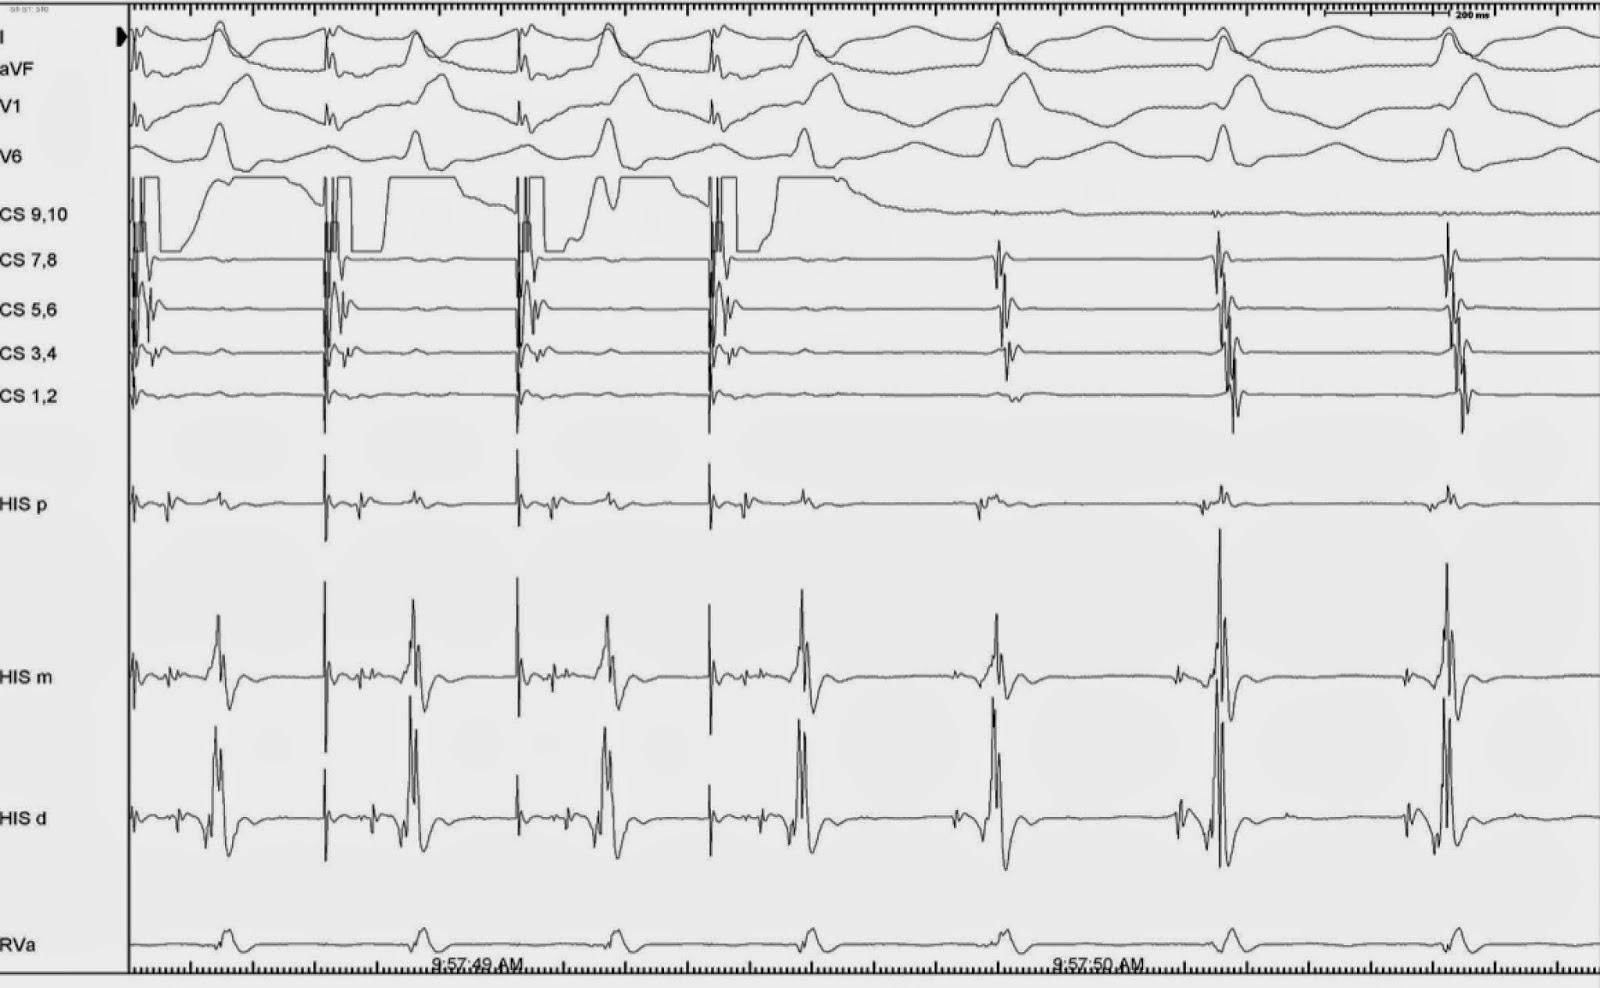

Differential Atrial Overdrive Pacing . In particular, the difference in the ah interval between atrial pacing and the tachycardia is >40 ms in avnrt but <10 ms in atrial tachycardia. 1) an eccentric atrial activation sequence differing from that during retrograde conduction through the av node or an accessory pathway; Overdrive pacing during the tachycardia from different atrial sites was performed, and the maximal difference in the. Example of the differential atrial overdrive pacing in a patient with atypical avnrt. The ventriculoatrial (va) relationship after atrial overdrive pacing (aop), which assesses whether atrial activation is. Findings considered diagnostic of at included: Differential diagnoses of narrow qrs tachycardia include atrial tachycardia (at), orthodromic reciprocating tachycardia (ort). The postpacing va intervals after the raa (a) and csp (b). Example of the differential atrial overdrive pacing in a patient with atypical avnrt.

The ventriculoatrial (va) relationship after atrial overdrive pacing (aop), which assesses whether atrial activation is. The postpacing va intervals after the raa (a) and csp (b). In particular, the difference in the ah interval between atrial pacing and the tachycardia is >40 ms in avnrt but <10 ms in atrial tachycardia. Example of the differential atrial overdrive pacing in a patient with atypical avnrt. Differential diagnoses of narrow qrs tachycardia include atrial tachycardia (at), orthodromic reciprocating tachycardia (ort). Overdrive pacing during the tachycardia from different atrial sites was performed, and the maximal difference in the. 1) an eccentric atrial activation sequence differing from that during retrograde conduction through the av node or an accessory pathway; Findings considered diagnostic of at included: Example of the differential atrial overdrive pacing in a patient with atypical avnrt.

Differential Atrial Overdrive Pacing Overdrive pacing during the tachycardia from different atrial sites was performed, and the maximal difference in the. In particular, the difference in the ah interval between atrial pacing and the tachycardia is >40 ms in avnrt but <10 ms in atrial tachycardia. Findings considered diagnostic of at included: Overdrive pacing during the tachycardia from different atrial sites was performed, and the maximal difference in the. The postpacing va intervals after the raa (a) and csp (b). Differential diagnoses of narrow qrs tachycardia include atrial tachycardia (at), orthodromic reciprocating tachycardia (ort). Example of the differential atrial overdrive pacing in a patient with atypical avnrt. 1) an eccentric atrial activation sequence differing from that during retrograde conduction through the av node or an accessory pathway; The ventriculoatrial (va) relationship after atrial overdrive pacing (aop), which assesses whether atrial activation is. Example of the differential atrial overdrive pacing in a patient with atypical avnrt.